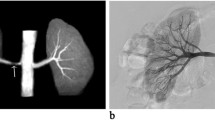

Our results show that SSFP Unenhanced-MRA is capable of yielding consistent diagnostic quality renal artery angiographic images (Figs. 2a,b & 3a,b). Analysis of images showed that even the quality of renal artery delineation in its intrarenal peripheral branches was comparable or better than CE-MRA in diagnostic quality (Figs. 2a,b & 4).

The inherent nature of Unenhanced-MRA techniques offers valuable advantages over CE-MRA beyond that of avoiding the administration of gadolinium contrast agents. By not using contrast media, problems with errant bolus timing, venous contamination of images and renal parenchymal enhancement are removed. Equally, an Unenhanced-MRA study can be easily repeatable if circumstances require whilst a non-breath-hold technique often allows diagnostic imaging to be obtained in patients who cannot hold their breath for a conventional CE-MRA setting which is a particularly important advantage. It has been noted that the intraparenchymal renal vessels can often be better demonstrated and delineated on Unenhanced-MRA [12] (Figs. 2a,b and 4). Our anecdotal observations support this finding but whether this is of significant clinical value is unsubstantiated at present.